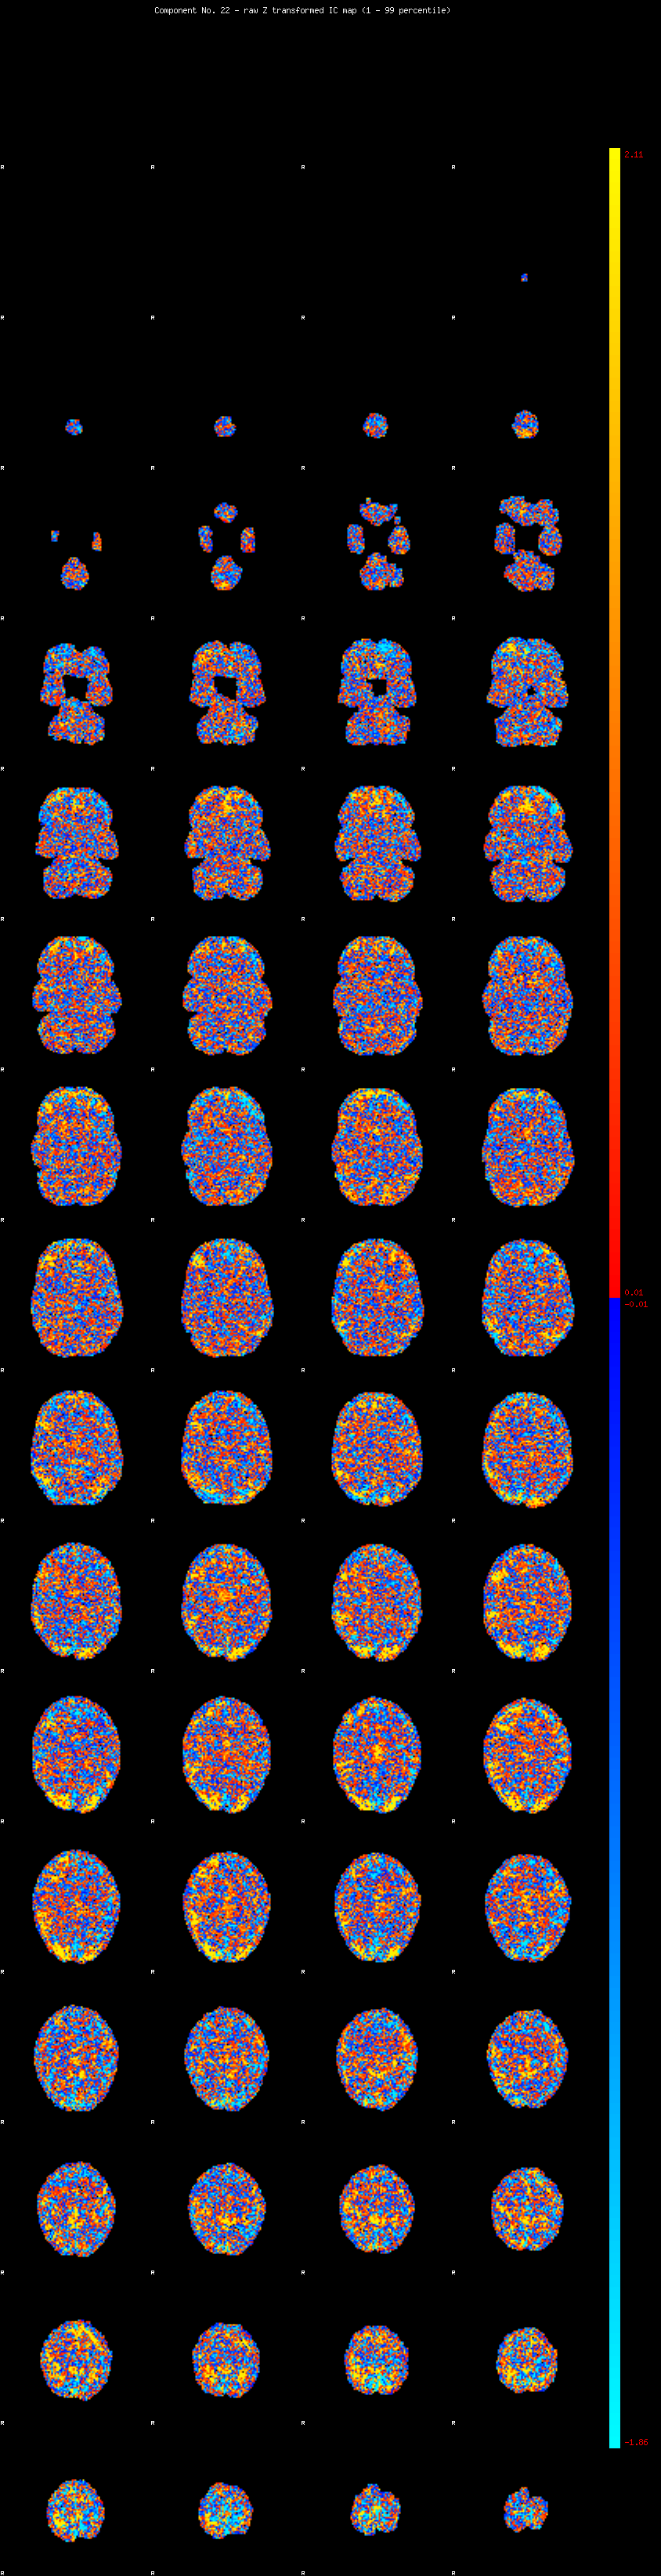

IC_22 Mixture Model fit

Means : -0.000000 2.829961 -2.729691

Vars : 1.000000 3.244758 1.171494

Prop. : 0.945495 0.038927 0.015578